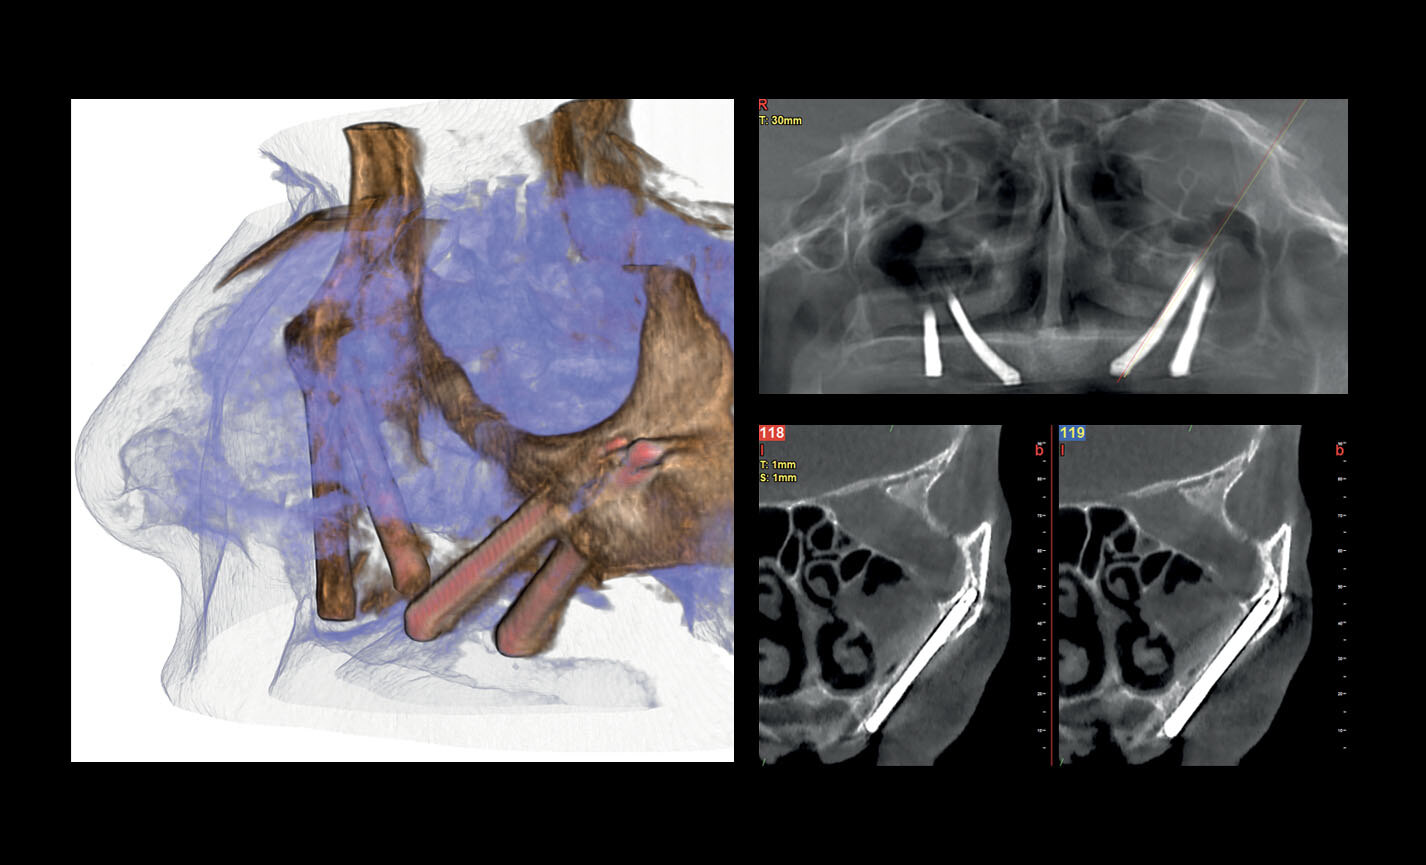

Évaluation des implants zygomatiques

Les volumes avec FOV 13 x 8 cm, ou 13 x 10 cm, représentent l’outil idéal pour la planification des implants zygomatiques. En effet, le diamètre de 13 cm est le seul qui permet d’inclure tout le zygoma dans le balayage, sans coupes.